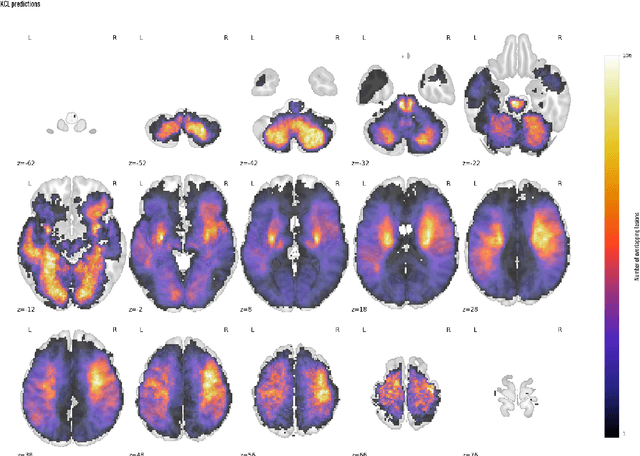

Abstract:Focal deficits in ischaemic stroke result from impaired perfusion downstream of a critical vascular occlusion. While parenchymal lesions are traditionally used to predict clinical deficits, the underlying pattern of disrupted perfusion provides information upstream of the lesion, potentially yielding earlier predictive and localizing signals. Such perfusion maps can be derived from routine CT angiography (CTA) widely deployed in clinical practice. Analysing computed perfusion maps from 1,393 CTA-imaged-patients with acute ischaemic stroke, we use deep generative inference to localise neural substrates of NIHSS sub-scores. We show that our approach replicates known lesion-deficit relations without knowledge of the lesion itself and reveals novel neural dependents. The high achieved anatomical fidelity suggests acute CTA-derived computed perfusion maps may be of substantial clinical-and-scientific value in rich phenotyping of acute stroke. Using only hyperacute imaging, deep generative inference could power highly expressive models of functional anatomical relations in ischaemic stroke within the pre-interventional window.

Abstract:Stroke is a leading cause of disability and death. Effective treatment decisions require early and informative vascular imaging. 4D perfusion imaging is ideal but rarely available within the first hour after stroke, whereas plain CT and CTA usually are. Hence, we propose a framework to extract a predicted perfusion map (PPM) derived from CT and CTA images. In all eighteen patients, we found significantly high spatial similarity (with average Spearman's correlation = 0.7893) between our predicted perfusion map (PPM) and the T-max map derived from 4D-CTP. Voxelwise correlations between the PPM and National Institutes of Health Stroke Scale (NIHSS) subscores for L/R hand motor, gaze, and language on a large cohort of 2,110 subjects reliably mapped symptoms to expected infarct locations. Therefore our PPM could serve as an alternative for 4D perfusion imaging, if the latter is unavailable, to investigate blood perfusion in the first hours after hospital admission.